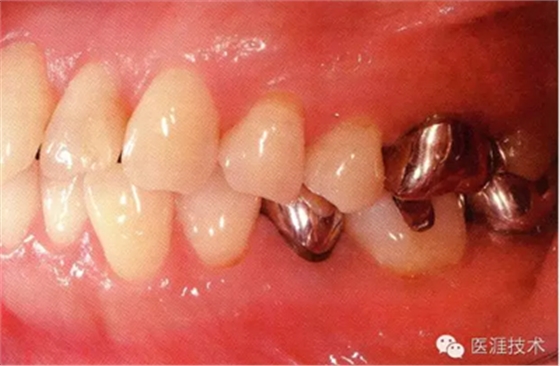

28歲女性的健康口腔內(nèi)部

圖為28歲女性,無特殊全身疾病,不抽煙。10年前來院就診保養(yǎng)3年,期間中斷過,現(xiàn)又開始。齲壞風險高,當初初診時已有好幾顆牙的鄰面有填充物,再填充了3牙的鄰面齲,現(xiàn)牙周組織健康。